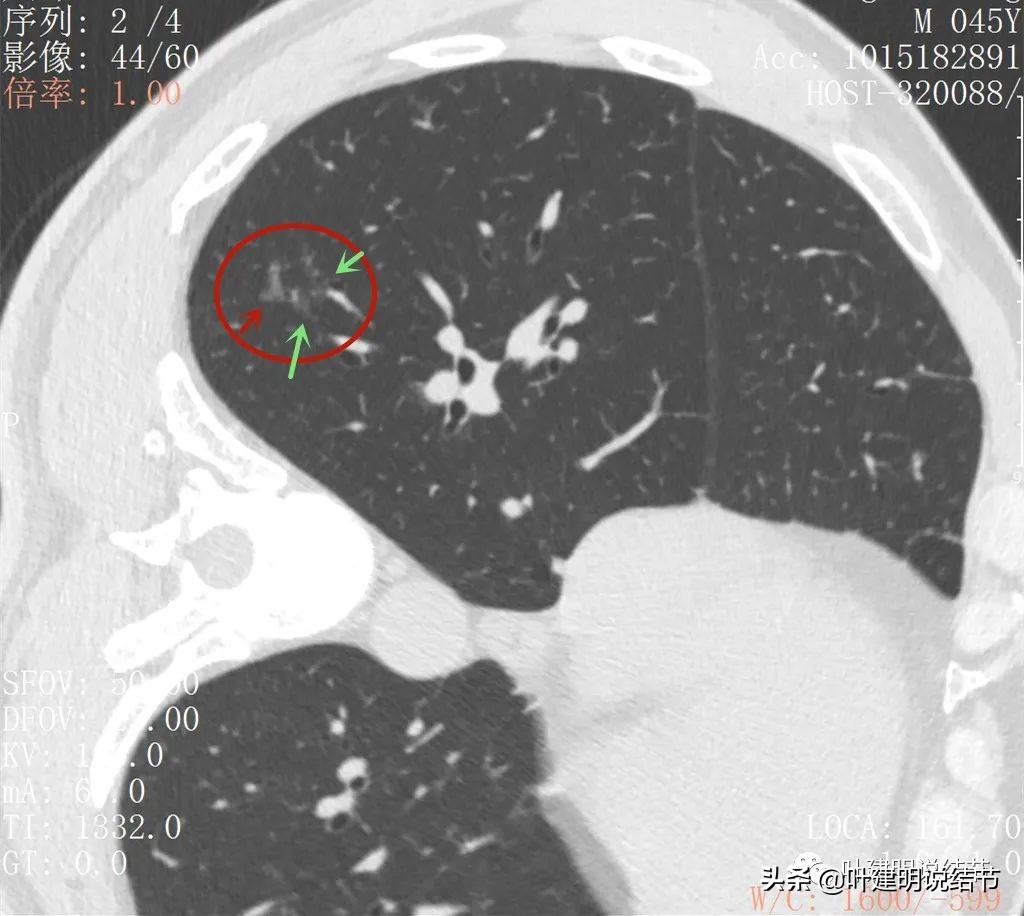

再来看薄层扫描:

病灶感觉很散在,但内部有扩张的细支气管(黄色箭头)、边缘略显不清(绿色箭头),部分有偏实性(粉色箭头)。

边缘血管异常增粗(桔色箭头),边缘显糊(绿色箭头),细支气管扩张(黄色箭头)

病灶似乎非圆形或类圆形,扩张的细支气管壁密度偏高(蓝色箭头),感觉比较僵硬(黄色箭头),病灶轮廓显模糊(黄色箭头)

扩张细支气管壁密度较高,病灶轮廓显糊

病灶边缘部分

右下叶背段有散在斑点状病灶,形态类似,但较主病灶小得多;左侧也有小结节状。

邻近病灶的下叶背段处也有形态类似的病变